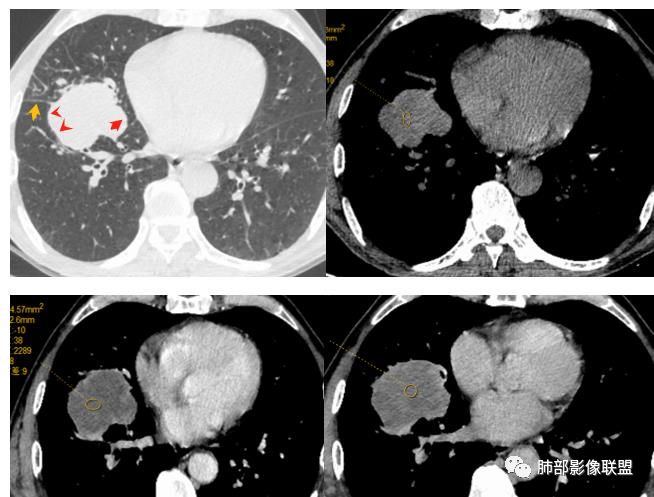

1.具有肉瘤的特性:肿瘤体积一般较大,直径约大于5cm,边缘清楚、光整,由于肿瘤生长迅速,可见大片坏死,坏死边界清楚;常见支气管推移。

2.具有癌些特性:如分叶、短毛刺、空洞,但是钙化及胸膜凹陷征少见,病灶往往是直接侵犯胸膜,可以远处转移,肺门及纵隔淋巴结可明显肿大;

3.强化方式:增强后病灶以环状强化为主,病灶周边多以癌组织为主,血供丰富,病灶中心区则以肉瘤成分为主,血供较差,易出现粘液样变性、坏死、出血,坏死边界清楚,所以增强CT对PSC与普通型肺癌有一定的鉴别价值。

1.本病例结合病理结果及影像综合分析,应该符合肉瘤样癌,上皮成分是腺癌为主;肿块的边缘毛刺、分叶及周围癌型淋巴管炎征象有符合腺癌的影像表现之处。

2.肿块巨大局部边缘膨隆、光整,坏死较彻底;明显跨叶生长(途经发育不全叶间裂或肺门,注意患者没有胸水),支气管阻塞伴推移等,这些更符合肉瘤的特性。

3.坏死区边界较清楚(皮囊样),环形强化明显,病灶内血管穿行等,都不符合我们常见的鳞癌。